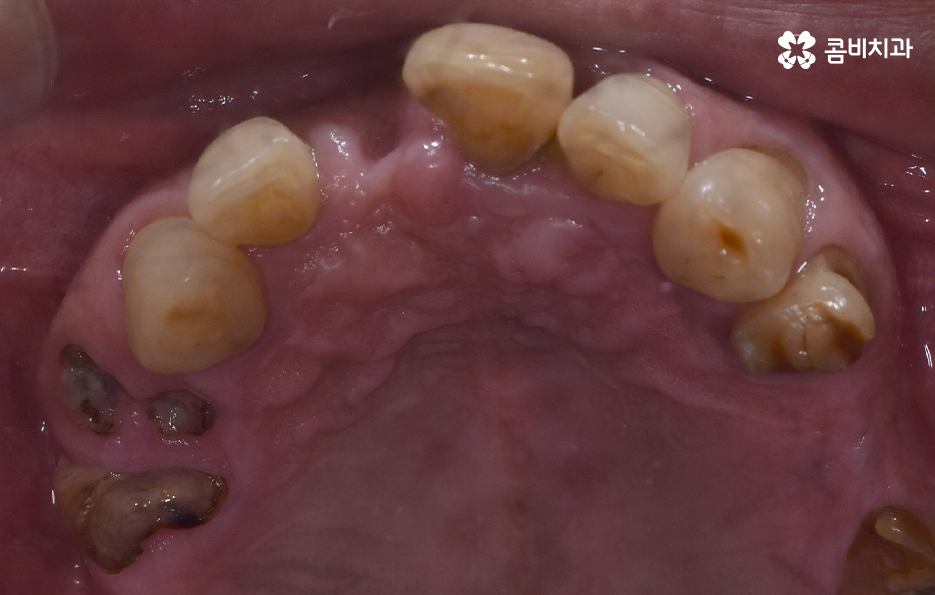

치주염으로 인해 잇몸이 내려앉고 치아의 뿌리가 흔들려서 발치했어요

위 환자분의 엑스레이 사진을 보면 치아의 뿌리 부분에 가깝게 잇몸이 내려앉은 것을 볼 수 있는데 치아의 구조에서 뿌리쪽은 법랑질이 없기 때문에 잇몸이 내려앉고 잇몸 뼈가 치주염으로 녹게 되면 치아가 너무 아파서 식사를 하기에도 어렵고 물 한잔만 마셔도 이가 시릴 정도로 일상에 지장을 느끼실 수 있어요